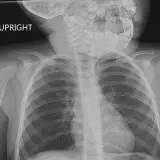

Over 2,100 interactive radiology cases, curated by radiologists for your level of training. Scroll, window, and view cases full screen — just like on PACS. Click linked findings in each writeup to jump straight to them on the image. Cases include sample reports, a focused discussion section, original illustrations, and videos.

PACSで期待されるツールを完備した完全インタラクティブな症例 — スクロール、ウィンドウ調整、ズーム、パン、計測、ROI、フルスクリーンモード。

重要な所見を症例画像上に直接ハイライトする豊富なアノテーション。症例解説内のリンクされた所見をクリックすると、スキャン上の正確な位置へジャンプできます。